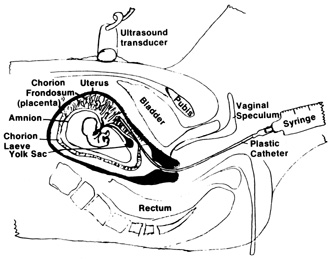

DNA probes for chromosomes 13, 18, 21, X, and Y. CHORIONIC VILLUS SAMPLING The indications for CVS are similar for amniocentesis, except for a few

rare genetic conditions that require chorionic villi for diagnosis.2 CVS is generally performed at 10 to 12 weeks' gestation. Similar

to other first trimester methods, CVS allows for results earlier that

can provide reassurance or allow for earlier and safer methods of pregnancy

termination. Similar to amniocentesis, CVS is performed under ultrasound

guidance. It can be performed either transabdominally or transcervically (Fig 4). Table 5 lists the contraindications and relative contraindications for CVS.

| Patient body habitus linking visualization—relative contraindication |  Fig. 4. Aspiration method of chorionic villi sampling. Ultrasound is used to localize

the chorionic frondosum and guide the aspirating catheter into

position. Syringe suction is used to trap and withdraw villi into the

catheter. Fig. 4. Aspiration method of chorionic villi sampling. Ultrasound is used to localize

the chorionic frondosum and guide the aspirating catheter into

position. Syringe suction is used to trap and withdraw villi into the

catheter.